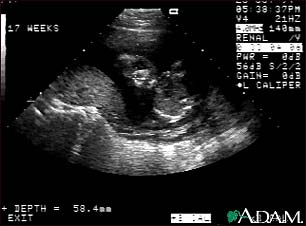

Ultrasound, normal fetus - face

This is a normal ultrasound of the fetus performed at 17 weeks gestation. The fetal face can be seen in the middle of the screen. The head is tilted left toward the placenta, which can be seen as a mound in the left of the ultrasound image. Both eyes are visible, and the area of white within the eye is the lens. Other facial features, such as the nose and mouth, are also visible.